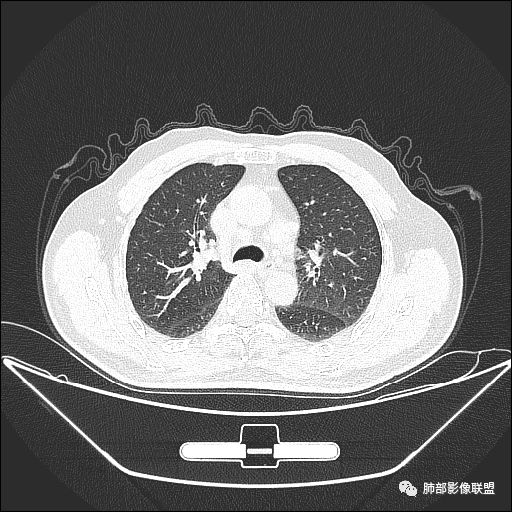

下面我们看看支气管都在吗?

内侧段是通畅但是受压的

外侧段一开始狭窄

但是远端通畅,所以我认为支气管都没有堵塞,不太可能是鳞癌

我们现在看主病灶,病灶紧贴叶裂:

我想看冠状位,就是看它长轴、病灶的整体形态

外围大、内带小

这时候我认为支气管最重要

支气管进入其中,远端粘液栓

我认为鉴别:结核?腺癌?

吴婧老师和南边老师都对该病例进行了深入分析。从支气管管壁的增厚,支气管狭窄后扩张,支气管粘液栓,病灶形态,到病灶不均匀强化及坏死彻底,到周边病灶及肺组织空气的潴留,加之纵隔内淋巴结肿大伴钙化等等,都支持慢性炎性病灶,尤其是结核。

现在小编来增加一个炎性另一个征象,是我们王兆宇老师原创的----就是墨西哥仙人掌征。

墨西哥仙人掌征---结核        影像上结核灶,粗大的均匀枝干,推测是支气管囊状扩张引起的,在非支气管区,形成圆形坏死囊群;如果这些坏死比较稀薄,又遇到扩张支气管,就会形成粗大的“墨西哥仙人掌”。结核引起的支气管近端炎症纤维化,可以造成支气管阻塞,从而将干酪样坏死物封堵在管腔内。仙人掌主干内部应该是干酪为主,稀薄的,具有流动性,时间久了会出现钙化。

结核坏死与鳞癌鉴别有一点是结核坏死没有方向性,鳞癌有。鳞癌靠近支气管近端部分,血供容易维持,不易坏死,所以坏死靠外侧。而结核干酪样坏死,把一定体积的流动性坏死物,包裹起来,什么形状最省料?坏死物包裹,表面积最省的自然是圆球形,而遇到支气管,坏死物一多,就把支气管撑大了。包裹物是就地取材,扩张的支气管就成了包裹结构。